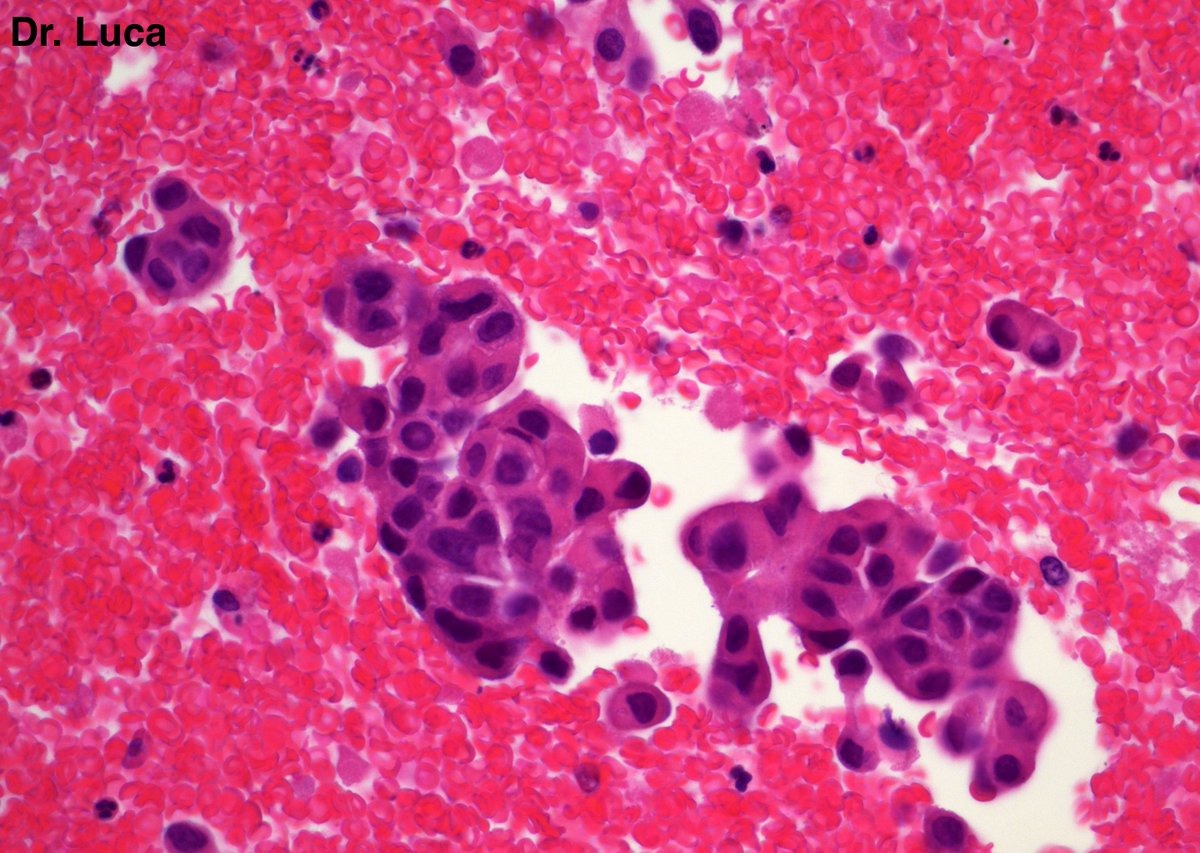

71yoM, bone metastasis, what's your quick H&E diagnosis? (no IHC) @AkgulMd @JPintoPath @slusagar @EKoubaMD @Pathmath1 @s_prendeville @goziemnweke @SumantaDas_7 @D4L14H @PoloniaAntonio @kriyer68 @md_kyle @kis_lorand @MarcosLepeMD @ivanaspath @pathobot #Pathology #PathTwitter

22

25

63